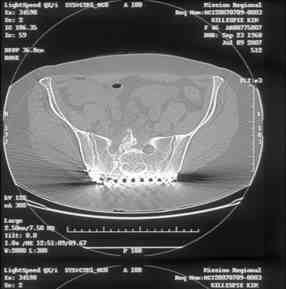

Looking for advice. This is a 48 yo non-smoking female s/p MCC 10 months ago. I do not have the initial injury films. She underwent ORIF as shown on attached file. She is having continued pain in low back/sacral region. Worse with sitting and prolonged walking. Has had pain since surgery. All of her wounds have healed uneventfully. Also has right hip pain laterally. No groin pain. Not aggravated with ROM of the hip. Infection work-up has been negative.

Any thoughts on the broken plate on the pelvic brim and the non-union on the anterior column. Doesn't seem like she's have pain from there.

Suggestions on treatment of sacral nonunion.

Here is a magnified view. Sorry about the quality but the CT was scanned into our system.